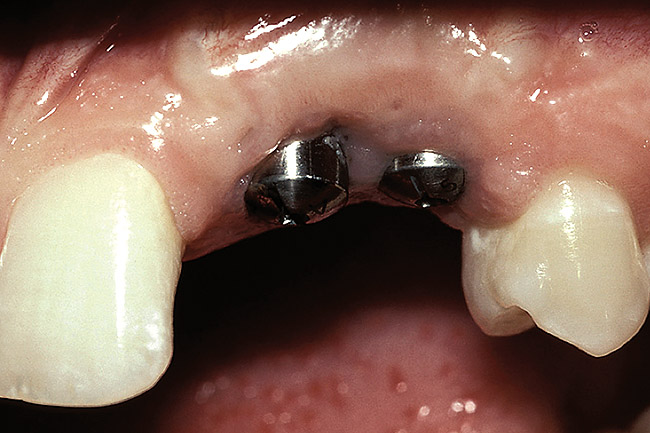

Figure 5  A patient presented needing both centrals extracted. Note the excellent papillary height and free gingival margin location.

Figure 5